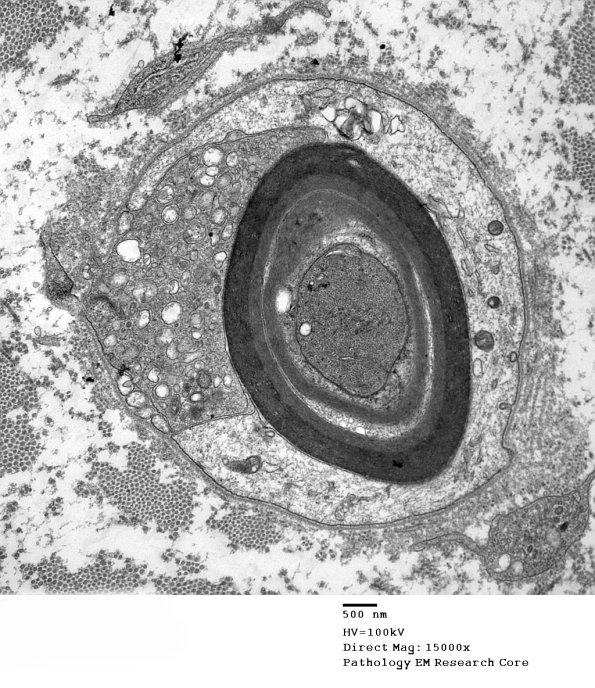

1D13A,B In this case the macrophage has little myelin debris at this stage. The axon may be quite dark and compacted in some cases. (electron micrographs)